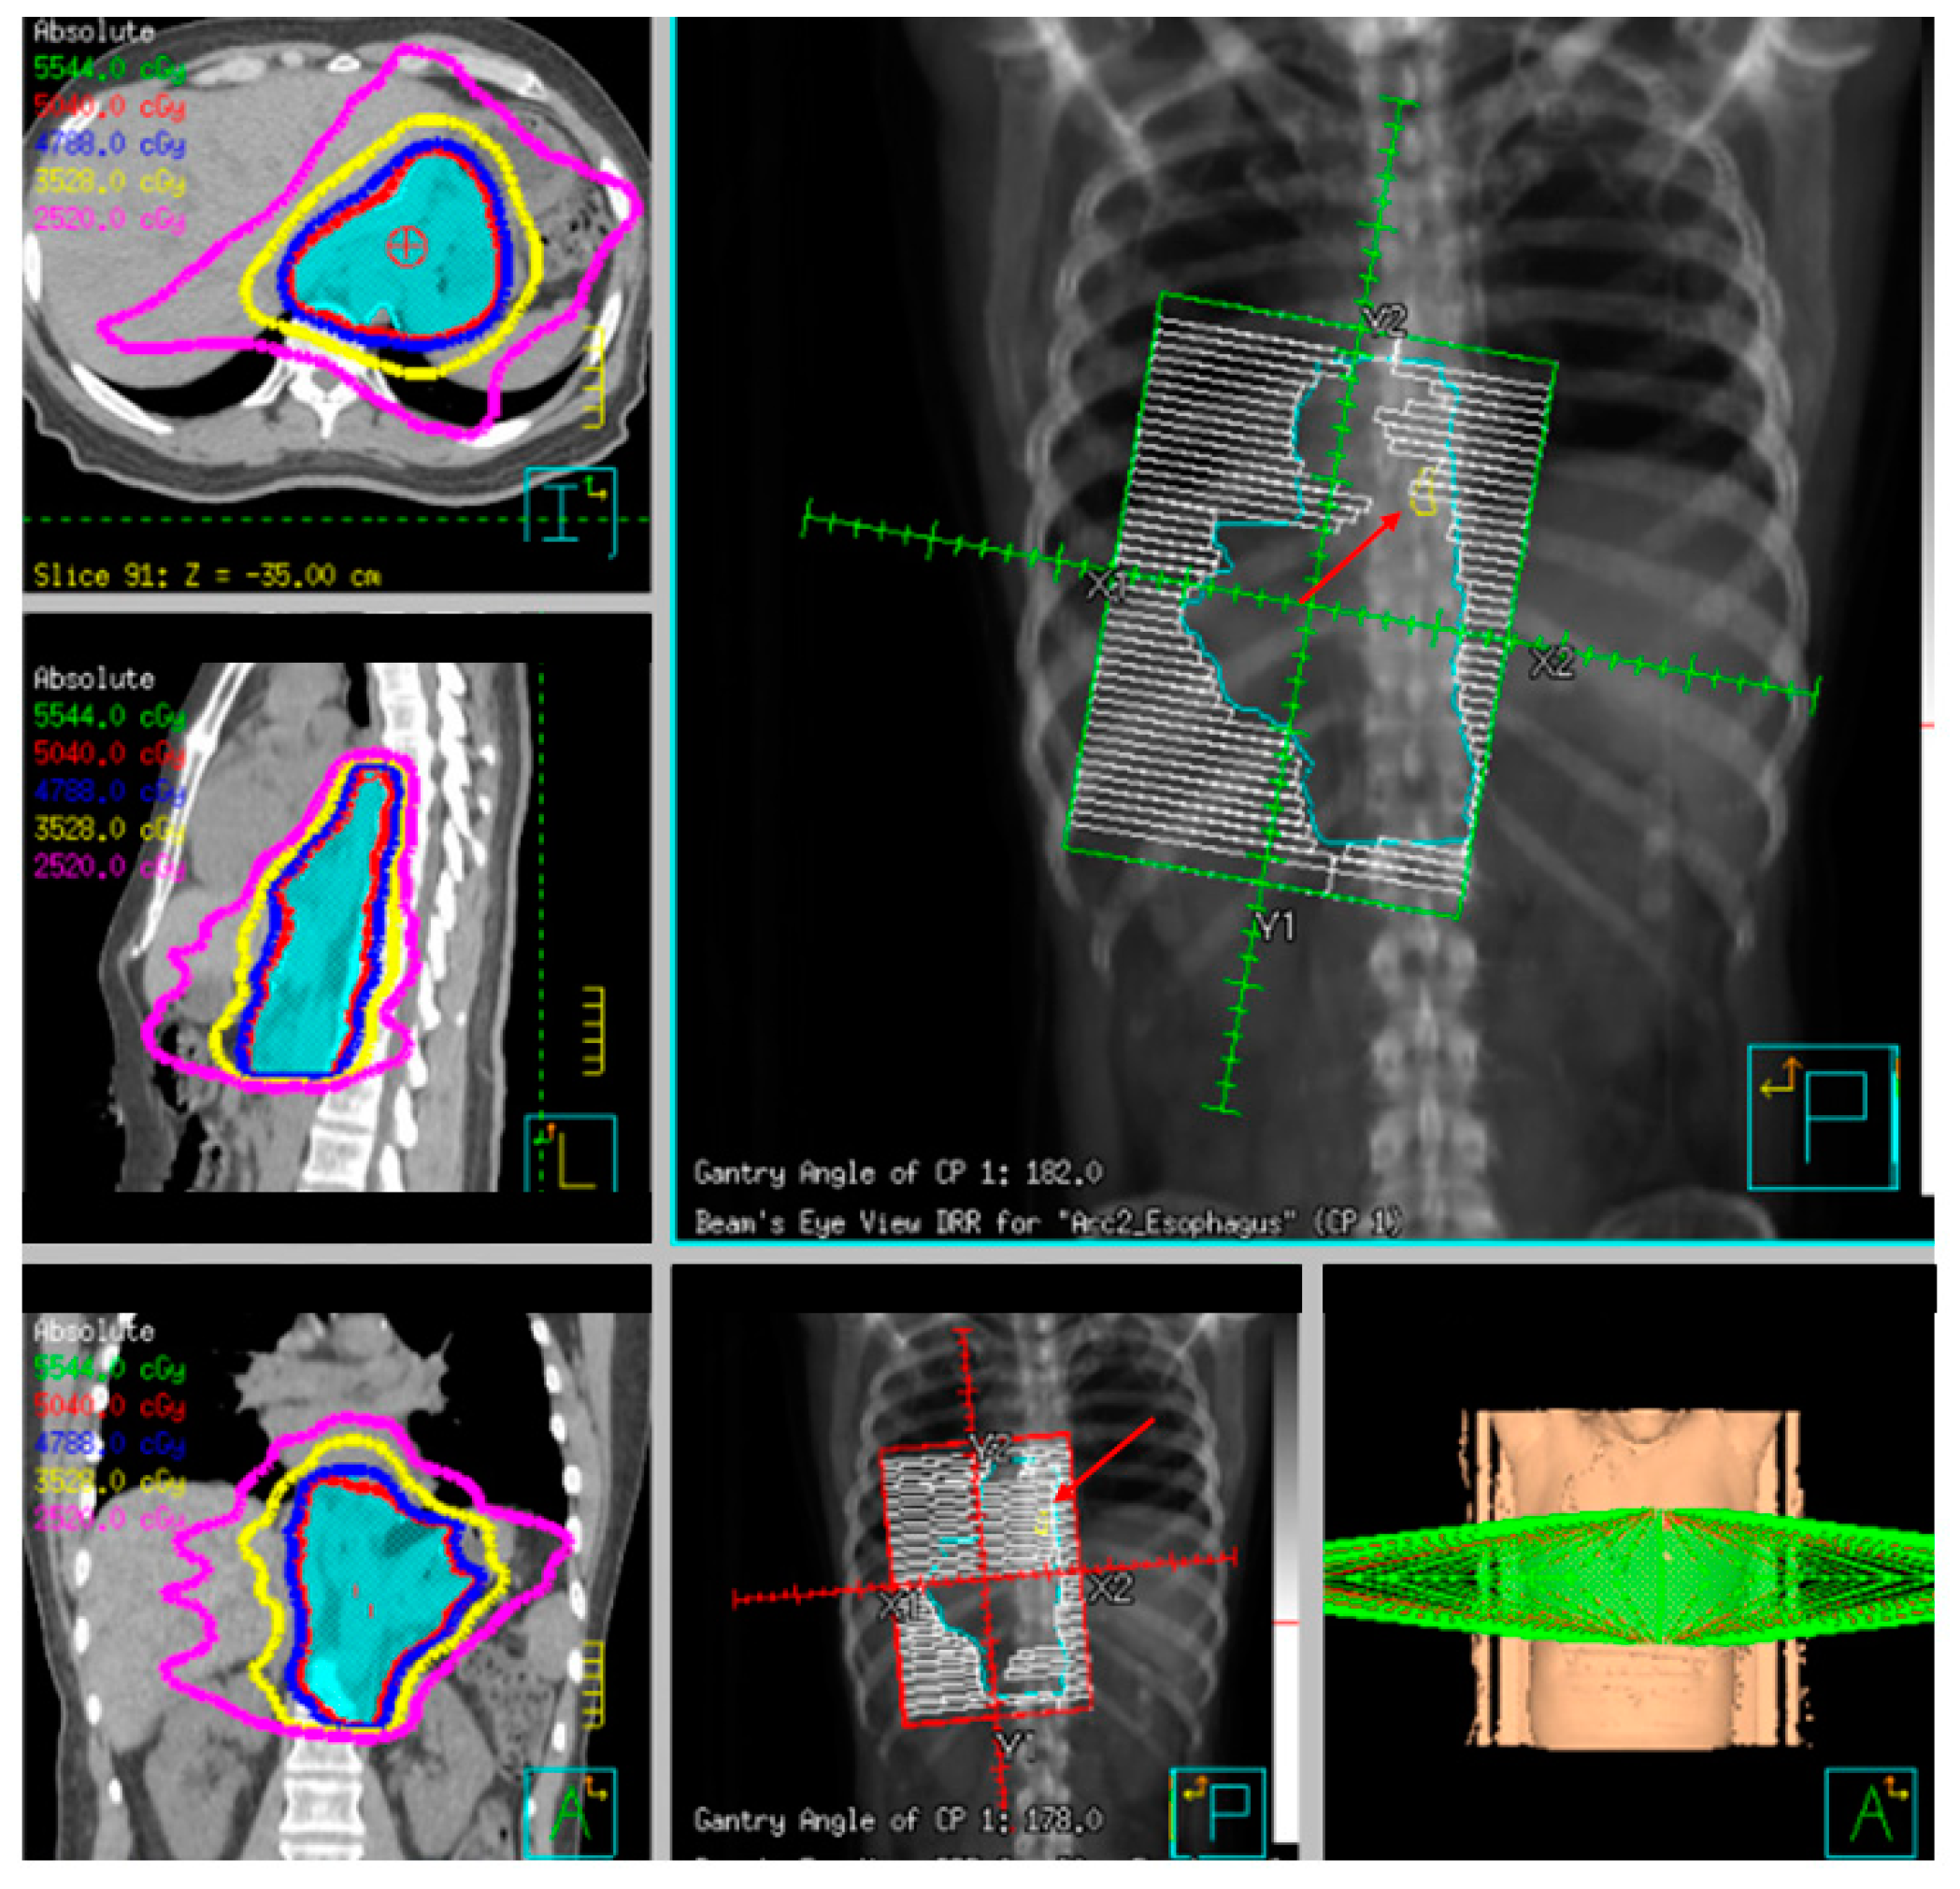

3.3. Multimodality Therapy for Locally Advanced Esophageal Cancer

3.5. Preoperative Chemoradiation

3.6. Definitive Radiation and Chemoradiation